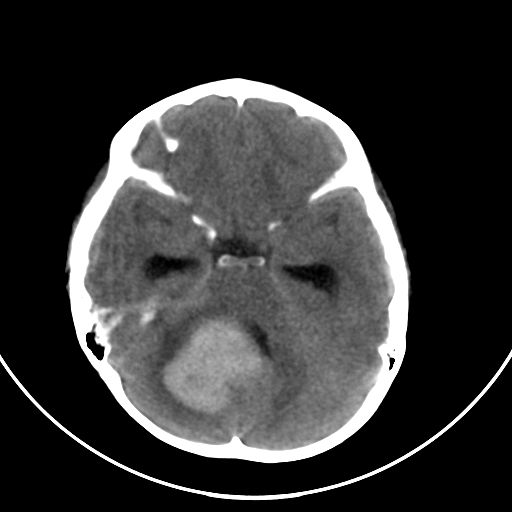

以下是引用zjzjr在2008-7-27 9:56:00的发言:[br]考虑髓母细胞瘤伴梗阻性脑积水.建议增强或mri

以下是引用子十在2008-7-27 9:53:00的发言:[br]考虑髓母细胞瘤